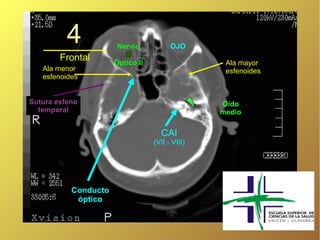

4 Nervio OJO Frontal Óptico II Ala mayor Ala menor esfenoides esfenoides Sutura esfeno Oído temporal medio CAI (VII - VIII) Conducto óptico